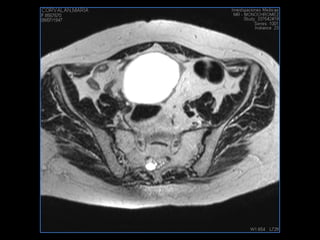

PROTOCOLO pelvis SAG T2, Y FAT SAT (FINOS) AXIAL T1  AX FAT SAT CON   GADOLINIO :  AX T1 Y COR T1 SAT: NO  FASE: RL THK: 3MM  COIL:  GAP: (FACTOR 1.4) 1MM FOV: 40 CM NEX:2 SINCRONIZACION RESPIRATORIA EN 3 O 4 CICLOS ALE